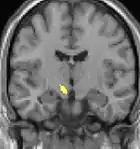

Hypothalamus

La théorie selon laquelle les AVF proviendraient d'une anomalie dans l'hypothalamus[48] est une des plus acceptées ; le Dr Peter James Goadsby[49], spécialiste australien a développé cette théorie. Cette thèse pourrait expliquer pourquoi les maux de tête se produisent avec une chronologie précise et régulière. L'un des rôles de l'hypothalamus est de réguler le rythme circadien. Des anomalies métaboliques ont d'ailleurs été signalées chez des patients.

Les images par tomographie à émission de positron indiquent les régions du cerveau qui sont activées lors de la douleur, par rapport aux périodes sans douleur. Elles montrent les régions du cerveau qui sont toujours actives durant la douleur en jaune/orange (appelé "matrice-douleur"). La zone au centre (dans les trois vues) est spécifiquement activée uniquement pendant la crise. Les photos sur la ligne du bas (effectuées par VBM) montrent les différences structurelles entre les patients souffrant d'AVF et des personnes saines : seulement une partie de l'hypothalamus est différente[50],[51].

Il semble exister des anomalies microstructurales hypothalamiques bilatérales (en l'occurrence l'existence d'une hypertrophie)[52] sans que l'on sache si ces anomalies sont la cause ou la conséquence de la répétition des crises.